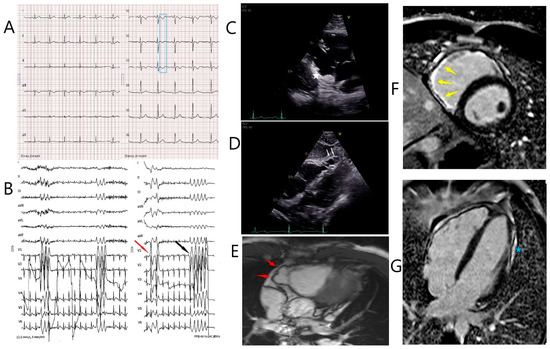

Biventricular Arrhythmogenic Cardiomyopathy Associated with a Novel Heterozygous Plakophilin-2 Early Truncating Variant